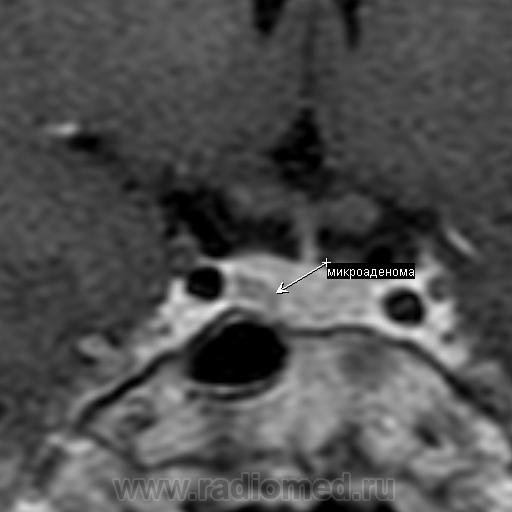

Представлены томограммы пациентки Б., 23 лет. Исследование назначено врачом-эндокринологом после лабораторного обледования. Высокие цифры пролактина. Пациентка существенных соматических жалоб не предъявляет. Акромегалии нет. Жалобы на невозможность забеременеть, нарушения менструального цикла. После проведения исследования в стандартных режимах и в режиме динамического сканирования с в/в контрастным усилением 20 мл ОМНИСКАН в правой доле гипофиза визуализируется дополнительное образование неправильной формы отстающее в накоплении контрастного вещества от здоровой ткани гипофиза. Выставлен диагноз: Микроаденома (пролактинома) гипофиза. Привожу данный клинический случай помятуя о разговоре в форуме.

Обратите внимание, коллеги, аденома не деформирует дно турецкого седла. Мне даже кажется, что за счет легкой асимметрии правая половина гипофиза расположена чуть выше левой.